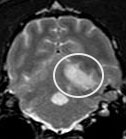

We also worked on the issue of thrombosis (clot formation) and thromboembolism (clot formation and migration) in Greyhounds. We recognized aortic, iliac, or femoral thrombosis as a cause of intermittent rear leg lameness in Greyhounds, and also identified the fact that retired racers are at high risk for brain or spinal cord thromboembolic events. The latter are acute, and cause severe neurologic signs (incoordination, paralysis, inability to move, excessive salivation, abnormal eye movement, etc). Mini-dose aspirin (1/4-1/2 of an 81 mg cardio aspirin once a day) results in rapid, marked clinical improvement in these patients. We evaluated another drugs (Plavix), but in our hands it was not very effective in Greyhounds (however, it works well in non-Greyhound breeds and in cats).